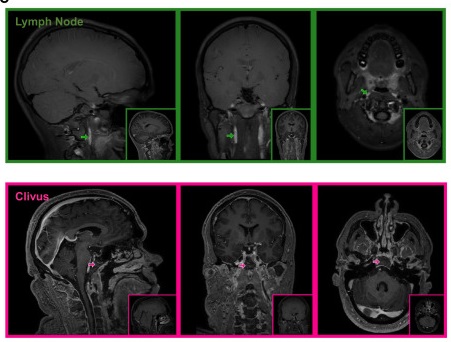

研究人員進一步透過高解析度影像分析人類腦組織,並與康乃爾大學合作,確認中腦膜動脈周圍存在典型淋巴管細胞結構,進一步證實MRI觀察到的液體流動確實屬於淋巴系統。

▲免疫螢光顯微鏡顯示人類中腦膜動脈(MMA)背側與腹側區段存在淋巴結構。

長期以來,科學界認為腦膜將大腦與免疫及淋巴系統隔離,但近十年來研究逐漸改觀。本次研究提供直接人體證據,顯示腦膜中的淋巴管負責將廢物輸送至全身淋巴系統,有助維持腦部健康。